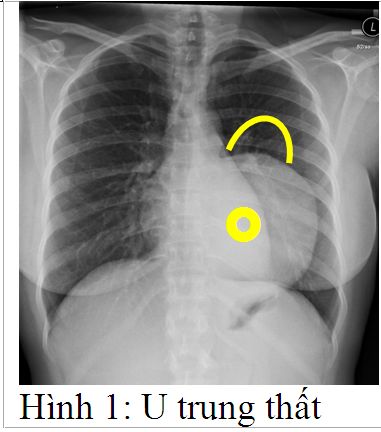

Hội chứng trung thất chính là các triệu chứng do khối U chèn ép các tạng trong trung thất gây ra, nó thường xuất hiện muộn khi khối U đã đạt đến một kích thước đáng kể để có thể gây chèn ép xung quanh